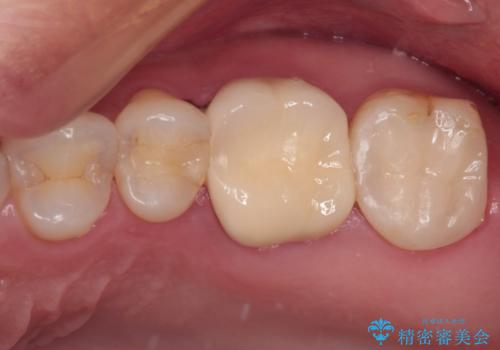

強い咬合力を負担する第一大臼歯であるため、根管治療後は速やかにオールセラミッククラウンにて補綴治療を行うこととしました。

初診時は神経組織の生活反応が認められましたが、2日後に処置を行ったときには、既に反応はなくなっている状態でした。

神経組織は壊死が始まっておりましたが、初回処置後には痛みを感じることもなくなり、2回目に無事に根管治療を終えることができました。